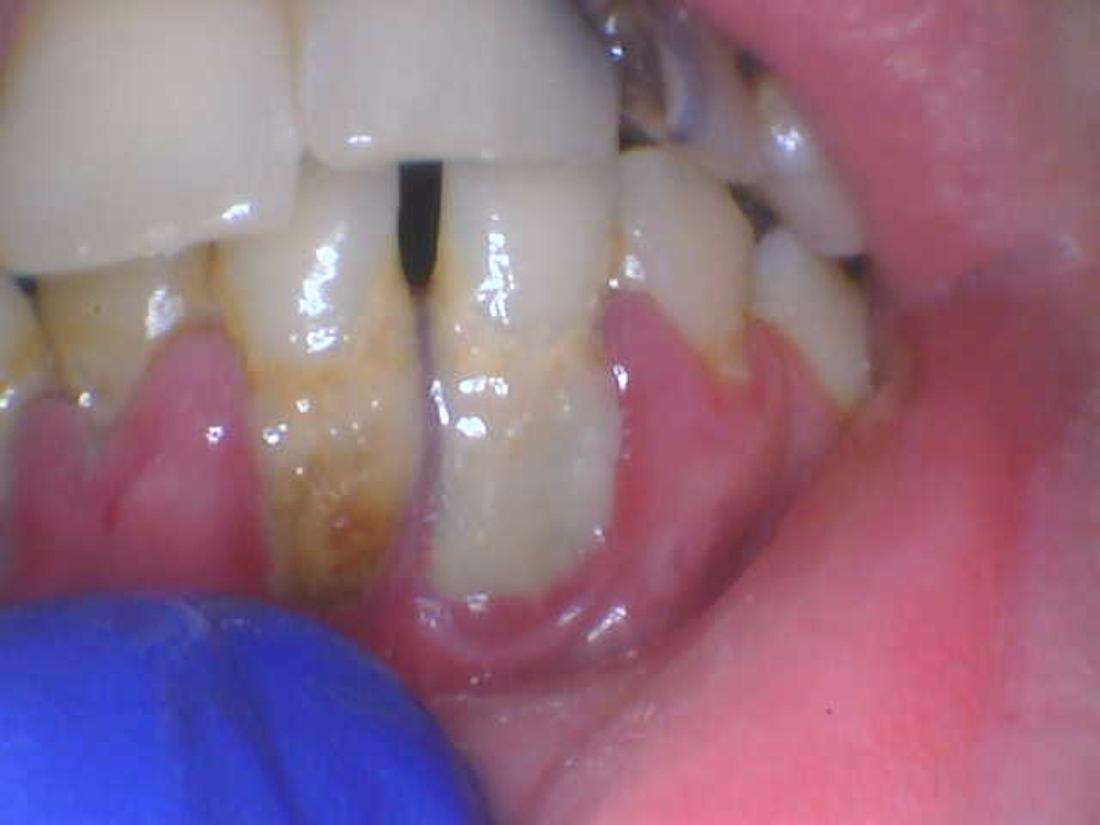

Scaling and Root Planing (SRP)

Before

After